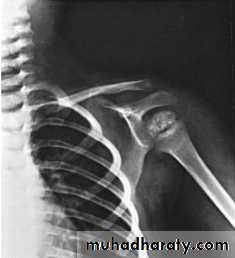

Radiological finding:

The distal femoral epiphysis is absent.

epiphyseal dysgenesis

deformity (“beaking”) of the 12th thoracic or 1st or 2nd lumbar vertebra.

skull X- ray: show large fontanels and wide sutures; intersutural (wormian) bones are common. The sella turcica is often enlarged and round; there may be erosion and thinning. Formation and eruption of teeth can be delayed.

Cardiac enlargement or pericardial effusion may be present.